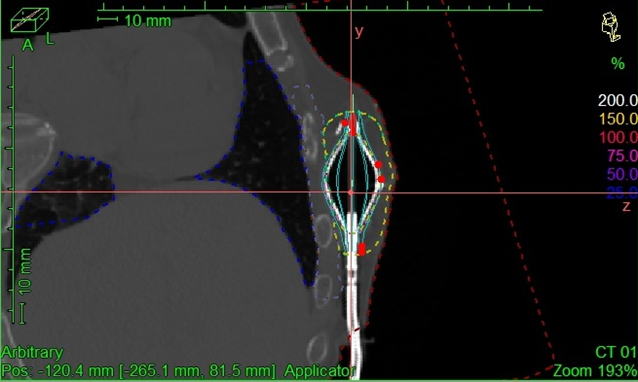

SAVI 治療計画の一例